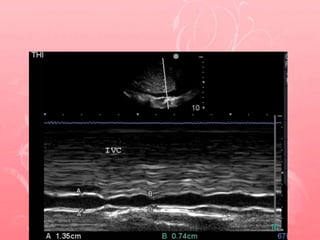

Theoritical method to measure IVC

2-D image of the IVC

entering the right

atrium

make sure IVC

visualization is not lost

during movements of

respiration

place a M-mode line

through the IVC 1 cm

caudal from its

junction with the

hepatic vein

record the M-mode

through 3 or 4

respiratory cycles.

Freeze the M-mode

image

using calipers,

measure the

maximum and

minimum diameter

from anterior to

posterior wall.

IVC diameter

• Low CVP is increasingly is likely as

• IVC diameter (IVCD) < 1 cm

• high CVP increasingly likely as IVCD > 2cm.